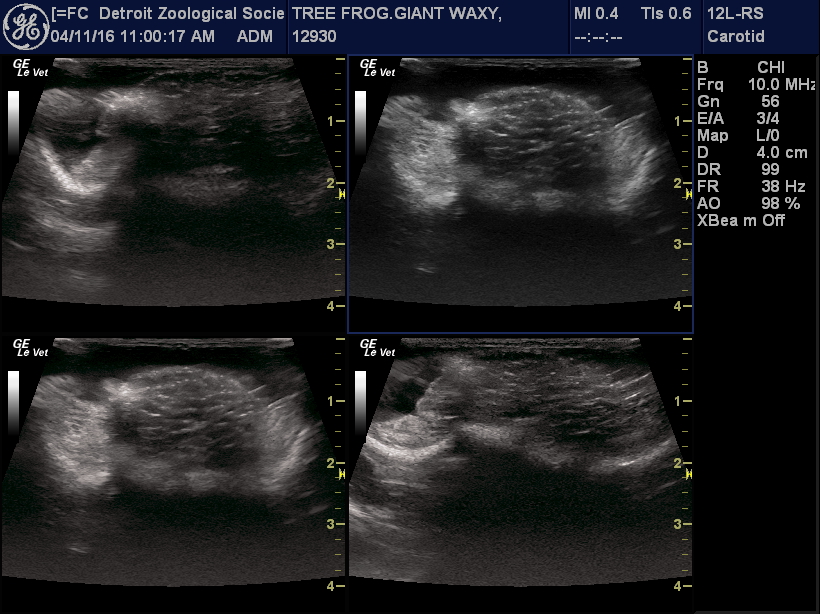

As zoo husbandry staff and amphibian reproductive experts have gained expertise, it has become clear that not all amphibians respond the same way to changes in their environment and established hormone protocols. Two years ago, we purchased a high frequency ultrasound probe, and we have found that we can monitor the appearance of the ovaries and follicles as they develop and mature within female frogs and toads. This provides a very powerful tool for understanding the impact of the husbandry and hormone treatments that we apply, and will allow us to establish assisted reproduction methods for other endangered species.

This season we have some exciting things planned, and have started the early work to check the females we are hoping to breed. Last week, we performed ultrasound exams on our three female giant waxy tree frogs, and were able to see that they are all developing large, follicle-filled ovaries. Based on the appearance of the follicles, we think that they will be ready to breed in the next few weeks to a month.